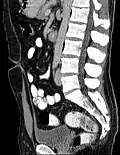

Midsagittal CT scan of a man's abdomen showing the urachus -